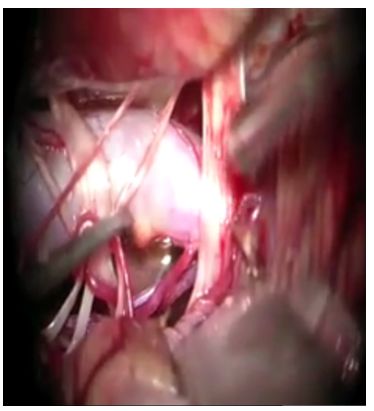

58岁男性患者,临床表现为左侧面肌痉挛,术前影像学检查诊断为基底动脉扩张延长症,导致左侧面神经受压(图1)。经患者同意后进行手术。手术采用远外侧入路,通过扩大枕下乙状窦后切口,显露基底动脉。基底动脉在中脑-脑桥连接处水平压迫左面神经根部。用muslin棉条制成悬带套住基底动脉,在斜坡硬脑膜上用19号针穿刺一孔;取一枚7mm直动脉瘤夹,将悬带末端栓系于动脉瘤夹一端,再将动脉瘤夹另一端穿入硬脑膜上破孔,把悬带锚定于硬脑膜上。通过拖曳悬带调整基底动脉的张力,最终将基底动脉从面神经上完全移开后,固定之(图2)。术后复查的CT及CTA显示,面神经不再受扩张、延长的基底动脉压迫(图3)。值得注意的是,由于手术野狭窄,在进行悬带套过基底动脉和移位的过程中,应避免过度牵拉致使穿支血管撕裂,一旦出血可能导致极其严重的后果。

图2. 术中照片。左图:显露面神经根部,可见粗大迂曲的基底动脉从内侧压迫面神经;中图:将muslin细棉条套过基底动脉;右图:用直动脉瘤夹将悬带固定于斜坡硬脑膜。